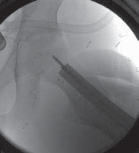

16. On the AP image the guide pin needs to be sufficiently proximal (superior) to provide enough room to permit the introduction of the seating chisel inferior to the guide pin (

TECH FIG 2A

).

17. On the frog-leg lateral view, the guide pin should lie in the middle of the femoral neck in line with the neck axis (

TECH FIG 2B

18. The seating chisel is then used to create the hole in the bone to accommodate the blade plate.

19. The seating chisel must be inserted perpendicular to the long axis of the femur if derotation is the only objective (

TECH FIG 2C

). Any deviation from the perpendicular on the AP view will lead to varus or valgus changes in the neck–shaft axis.

20. The face of the seating chisel should also be perpendicular to the long axis (in the sagittal plane) to prevent unintended flexion or extension through the osteotomy (

TECH FIG 2D

--- TECH FIG 2 • Intraoperative C-arm–guided insertion of the seating chisel for the blade plate.A. Insertion of the guide pin in the superior part of the neck at right angles to the long axis of the femur. B. Position of the guide pin along the midfemoral neck axis in the frog-leg lateral view. C. Position of the seating chisel parallel to the guide pin and perpendicular to the long axis of the femur. D. Position of the seating chisel parallel to the guide pin and along the midfemoral neck axis on the frog-leg lateral view. E. The seating chisel is backed out from its final position to disimpact the chisel before the osteotomy.Pr FiAE